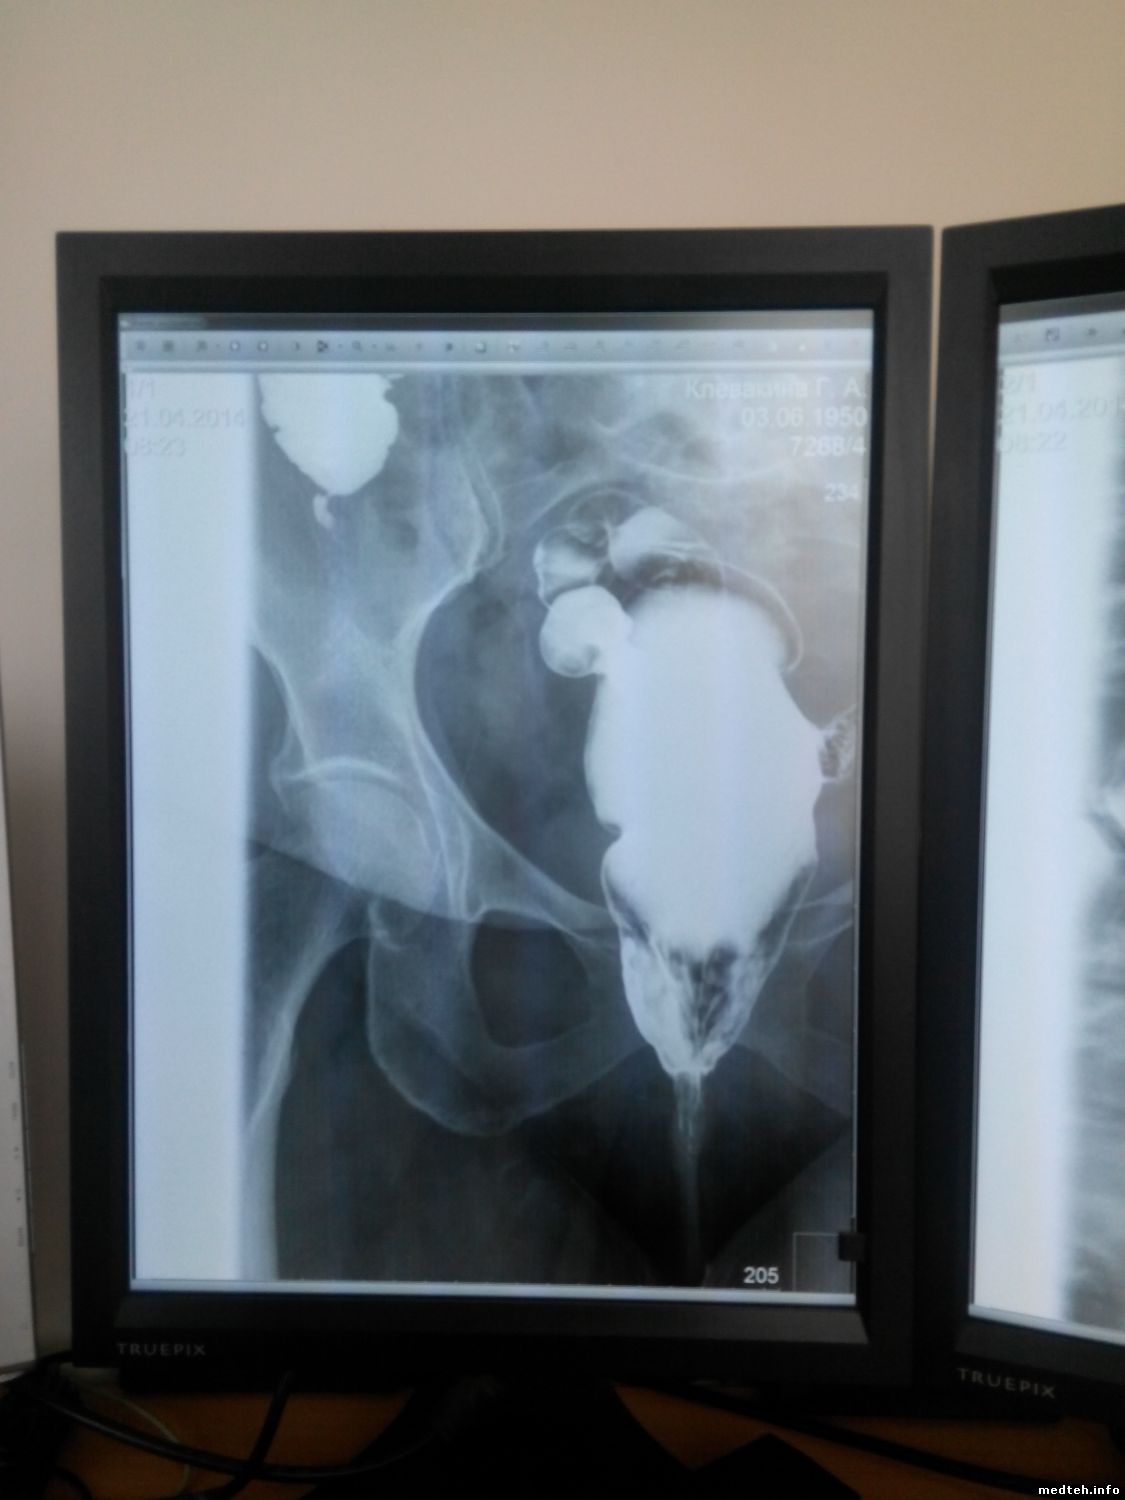

На скопии ,снимки получаются размазанными и обрезанными.

5664084.jpg (75.9 Kb)